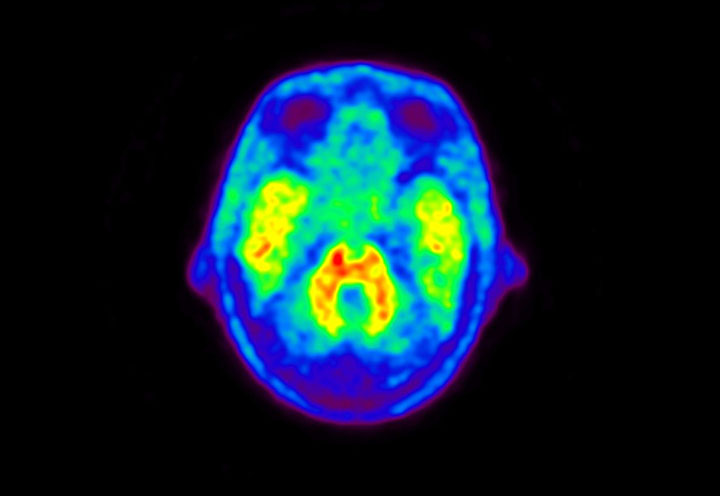

Head / Case5 : Amyloid

Courtesy : Kindai University Hospital

- Imaging protocol

- Injected dose: 4.27 MBq/kg, 18F-Flutemetamol

- Uptake time: 99 minutes

- Scan time: 20 minutes